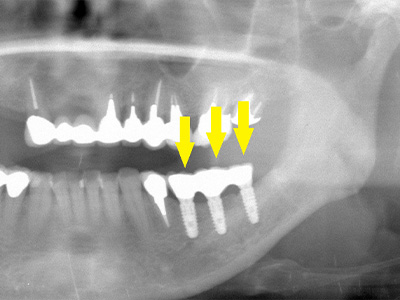

写真が、インプラント埋入手術後、右写真が上部構造装着後のレントゲン写真です。 -

移植骨片と周囲骨とは、ほとんど境目が分からなくなっています。

これが、遊離自家骨移植術です。